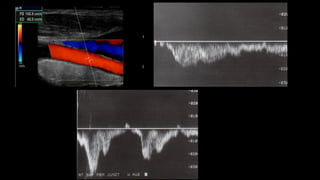

Figura 3 Doppler espectral con corte transversal evidencia

una VSM suficiente ante las maniobras de Valsalva.

Doppler de miembrosinferiores en la insuficiencia venosa 5 VSM VFC Figura 8 Corte longitudinal a nivel del ostium, donde se debe hacer la medición del diámetro de la VSM. - Se debe mencionar y evaluar la existencia de venas vari- cosas que no tengan relación con las safenas, así como también hay que establecer cuál es su procedencia (por ejemplo: vena pélvica), ya que la ligadura de las safenas puede no ser necesaria16 . En síntesis, el objetivo del examen es determinar el punto de fuga, la presencia de venas epifasciales insuficientes y el punto de reentrada, indicando la existencia de perforantes insuficientes y su localización. Parámetros a evaluar en el paciente safenectomizado con tratamiento de termo obliteración 1) Buscar si se evidencian tramos de safena e informar dónde comienzan y terminan. 2) Es importante tener en cuenta que en la etapa posquirúr- gica inmediata se pueden ver imágenes hiperecogénicas en la luz de la vena, habitualmente secundarias al tra- tamiento de termo obliteración con láser. Esto no debe ser confundido con trombosis y tiene que ser informado como safena termo-obliterada. ARTICLE+Model RARD-60; No. of Pages 8 6 Vena perforante Vena perforante insuficiente HD P T R 12,03,0 P T R 12,03,0 Figura 10 Vena perforante mayor de 3 mm con reflujo en el

reverso ante lasmaniobras de Valsalva en la unión safena- femoral (viraje de color rojo, en descanso a color azul, en Valsalva). +0,86 m/s –0,864 s m/s –0,11 +0,11 Vena femoral VSM Figura 5 Imagen que demuestra el cierre valvular correcto sin reflujo en la VSM con el Doppler color y espectral. Figura 7 Insuficiencia de la VSM en el tercio medio del m ante las maniobras de Valsalva. - Para examinar el eje de la VSP, con el paciente de e das al operador, se realizan cortes transversales en la posterior de la pantorrilla (de caudal a cefálico), vis zando la vena safena parva y calculando el reflujo e distintos niveles. Debe consignarse si es o no tortuo a qué altura desemboca en la vena poplítea (si es lo hace)15 , midiendo la distancia desde la planta del A su vez, hay que evaluar la presencia o no de la safena parva del muslo y, en caso de que esté prese definir si esta es suficiente o insuficiente. - A nivel del hueco poplíteo se busca la existencia de re en la vena poplítea. - Si se descubre insuficiencia de la VSP, también debe indicar si el ostium está involucrado o si el reflujo se i más caudalmente, si hay presencia de venas epifasc dilatadas y los puntos de reentrada del flujo. - Es necesario explorar las venas tibiales posteriores, a riores y peroneas. ARTICLE IN PRESSRARD-60; No. of Pages 8 4 H. Berardi, A. Ciccioli VSM Izquierda + ,07 – ,07 m/s +55,90 –54,98 cm/s 2 1 0 Vena femoral VSM 5,3s Figura 3 Doppler espectral con corte transversal evidencia una VSM suficiente ante las maniobras de Valsalva. HD 20 10 0 10 20 T R 12,03,0 P VSM HD Figura 6 Corte transversal de la VSM que muestra un aumento de las velocidades anterógradas (por encima de la línea de base), ante las maniobras de Valsalva.